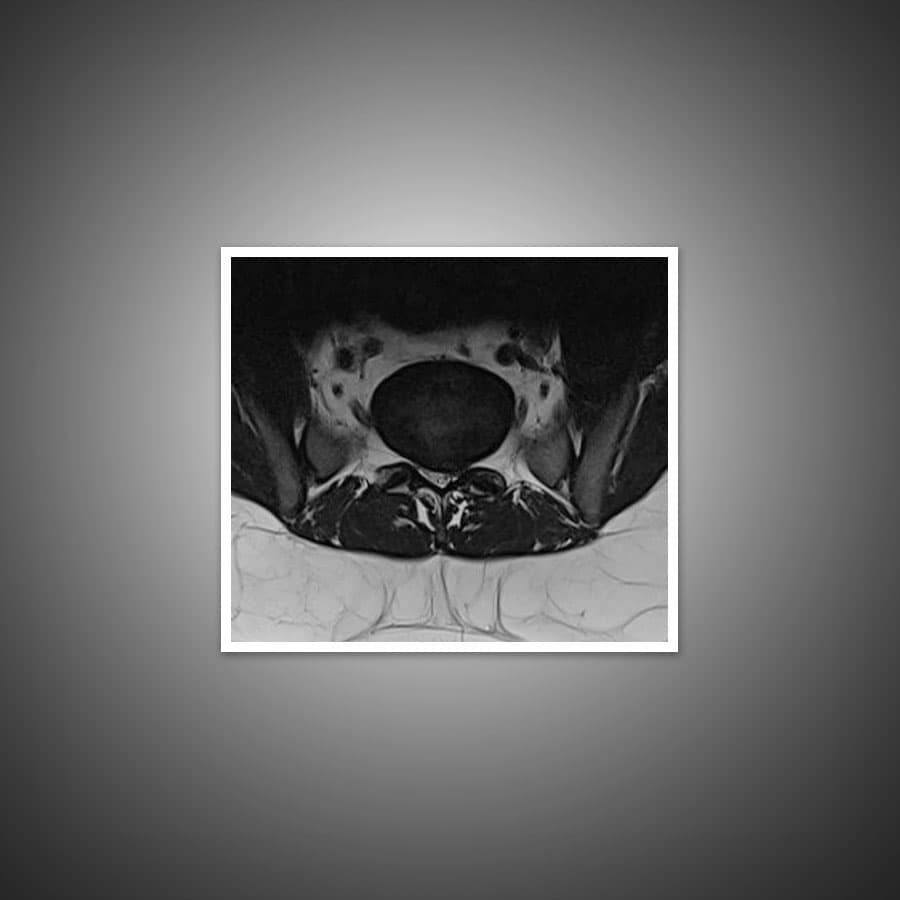

The most common imaging for herniated disc is MRI. X-rays of the affected region are usually added to get a better evaluation of the vertebra. CT scan and myelogram will only be ordered if the initial scans using MRI and X-rays are inconclusive in helping to form a clear diagnosis.